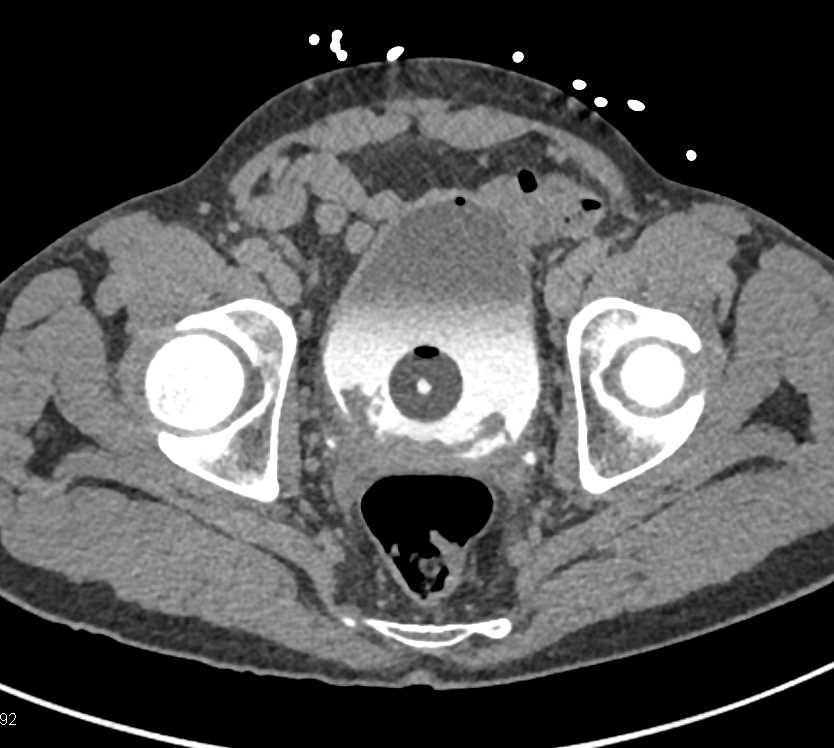

Incidental Bladder Cancer